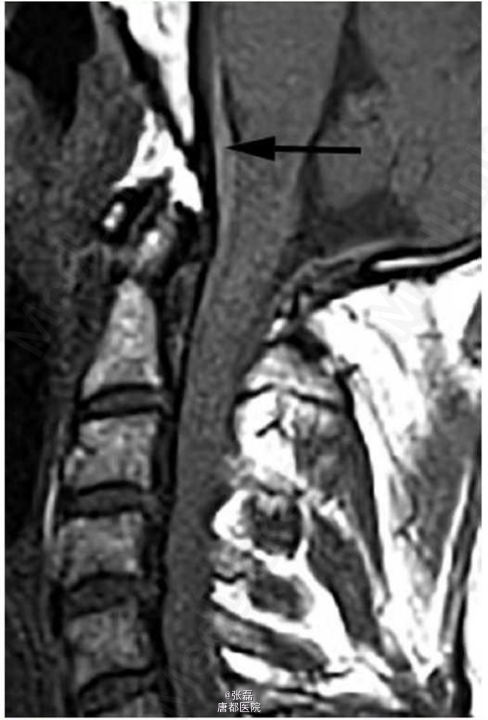

患者男性,51岁,因活动中突发后背疼痛前来急诊科。

神志清楚,定向正常,痛苦面容,生命体征为:体温 35.7°C,心率 86 次 / 分,血压 127/77 mmHg,呼吸 18 次 / 分,血氧饱和度 98%(未吸氧)。体格检查示大汗,包括心脏与神经系统查体在内均未见异常。首次治疗予以患者大剂量静脉用麻醉药物及止吐药物,但疼痛未缓解。

急诊行 T1-T5 椎板切除术与减压术。术后诊断为蛛网膜下腔出血肿块在髓内扩大,导致脊髓受压以及神经系统功能障碍。病理检查提示为血肿。随后,患者接受了脊髓血管造影进一步评估可能的出血源。血管造影未发现动静脉畸形或其他血管畸形。